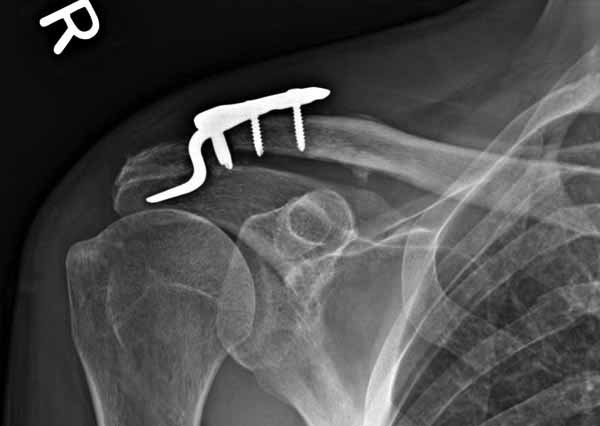

Re: ключичная пластинка

Отправитель: Серж 24 Июнь 2011, 13:41

foto

2.JPG